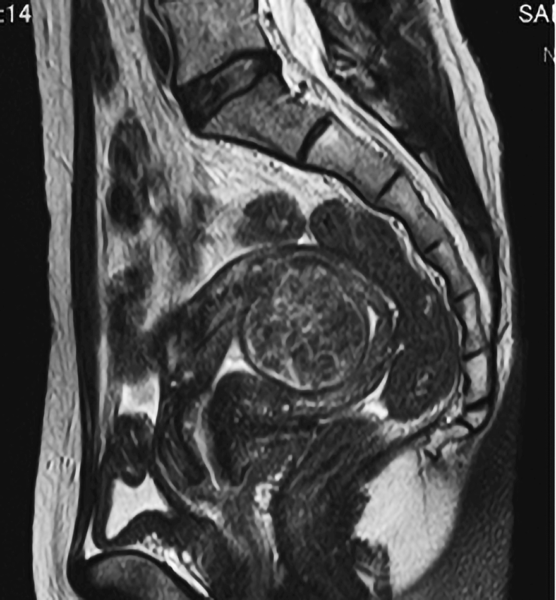

以下のMRI画像は下腹部縦切りの断面で画面右が背中です。

4cmの粘膜下筋腫で腹腔鏡手術の予定でしたが、子宮鏡で取り妊娠出産しました。子宮の内側の筋腫は腹腔鏡では子宮筋層を大きく切りますが、子宮鏡は筋層を切らずにすみます。

腹腔鏡手術は普及しましたが、子宮鏡ができる医師はまだ少ないのが現実です。腹腔鏡を行なう医師が「おなかに傷を作らず翌日退院でき帝王切開の必要がない子宮鏡」も行なうようになることが望まれます。